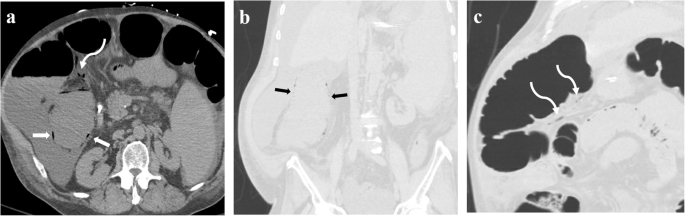

Fifty-nine-year-old male obtained non-contrast CT of abdomen and pelvis for the concern of small-bowel obstruction, who was not diagnosed to have coronavirus disease 2019 prior to CT. Patient’s history was notable for coronary artery bypass surgery 8 days ago and non-alcoholic steatohepatitis-induced liver cirrhosis. Axial (a) and coronal (b and c) CT images demonstrated fluid filled ascending colon with pneumatosis (white straight arrow in a, black straight arrow in b), as well as linear branching air along the mesenteric vessels (white curved arrow in a and c), concerning for ischemic colitis. Subsequently, patient underwent extended right hemicolectomy and was confirmed to have transmural ischemia and necrosis of the ascending colon